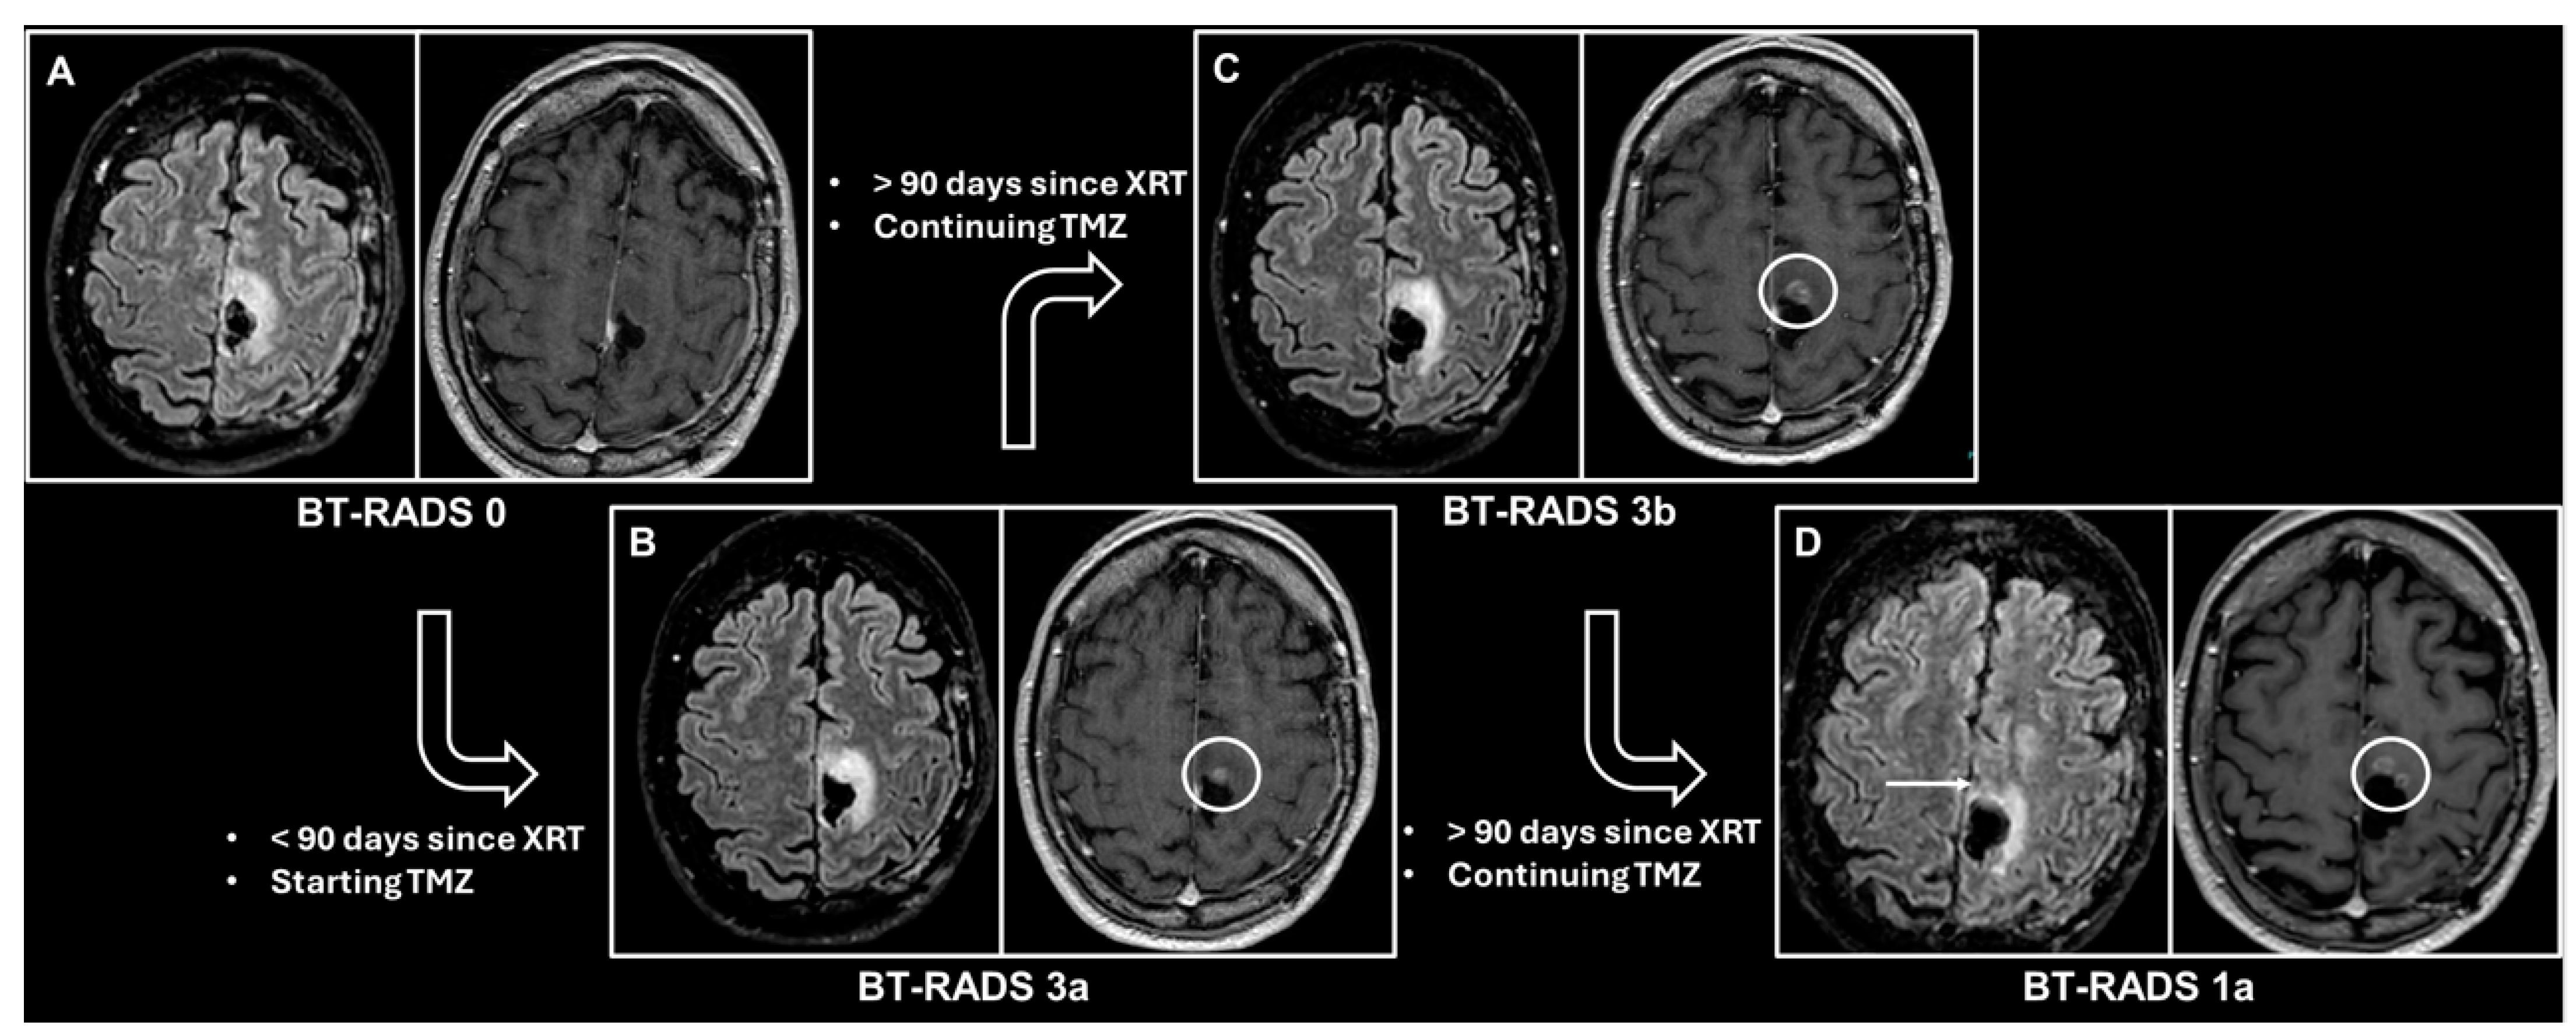

| 0 | New baseline, incomplete study, or otherwise unable to categorize. | Continued follow-up; no change. |

| 1 (improvement) | Reduction in enhancing component, FLAIR component, mass effect, or resolution of lesions. 1a—Reflects decreasing tumor burden and/or improving treatment effect. 1b—Effect from medications such as increasing steroids or initiating Avastin. | |

| 2 (stable) | No appreciable change. | |

| 3 (worsening) | Increase in enhancing component, FLAIR component, and/or mass effect. 3a (<90 days since radiation therapy)—Represents treatment effects, including radiation therapy and medications. 3b (>90 days since radiation therapy)—Represents an indeterminate mix of treatment effect and tumor worsening. 3c (<25% worsening in FLAIR and enhancement and first-time worse or new indeterminate lesion outside the expected high-dose radiation field)—Represents increasing tumor burden. | Decreased time interval of follow-up. Consider change in management in 3c. |

| 4 (definitely worsening) | Increase (>25% or <25% if progressively worsened over more than 1 study) in enhancing component, FLAIR component, mass effect, and/or new definitive lesion outside the expected high-dose radiation field. Worsening of imaging findings highly suspicious for tumor progression. | Change in management. |